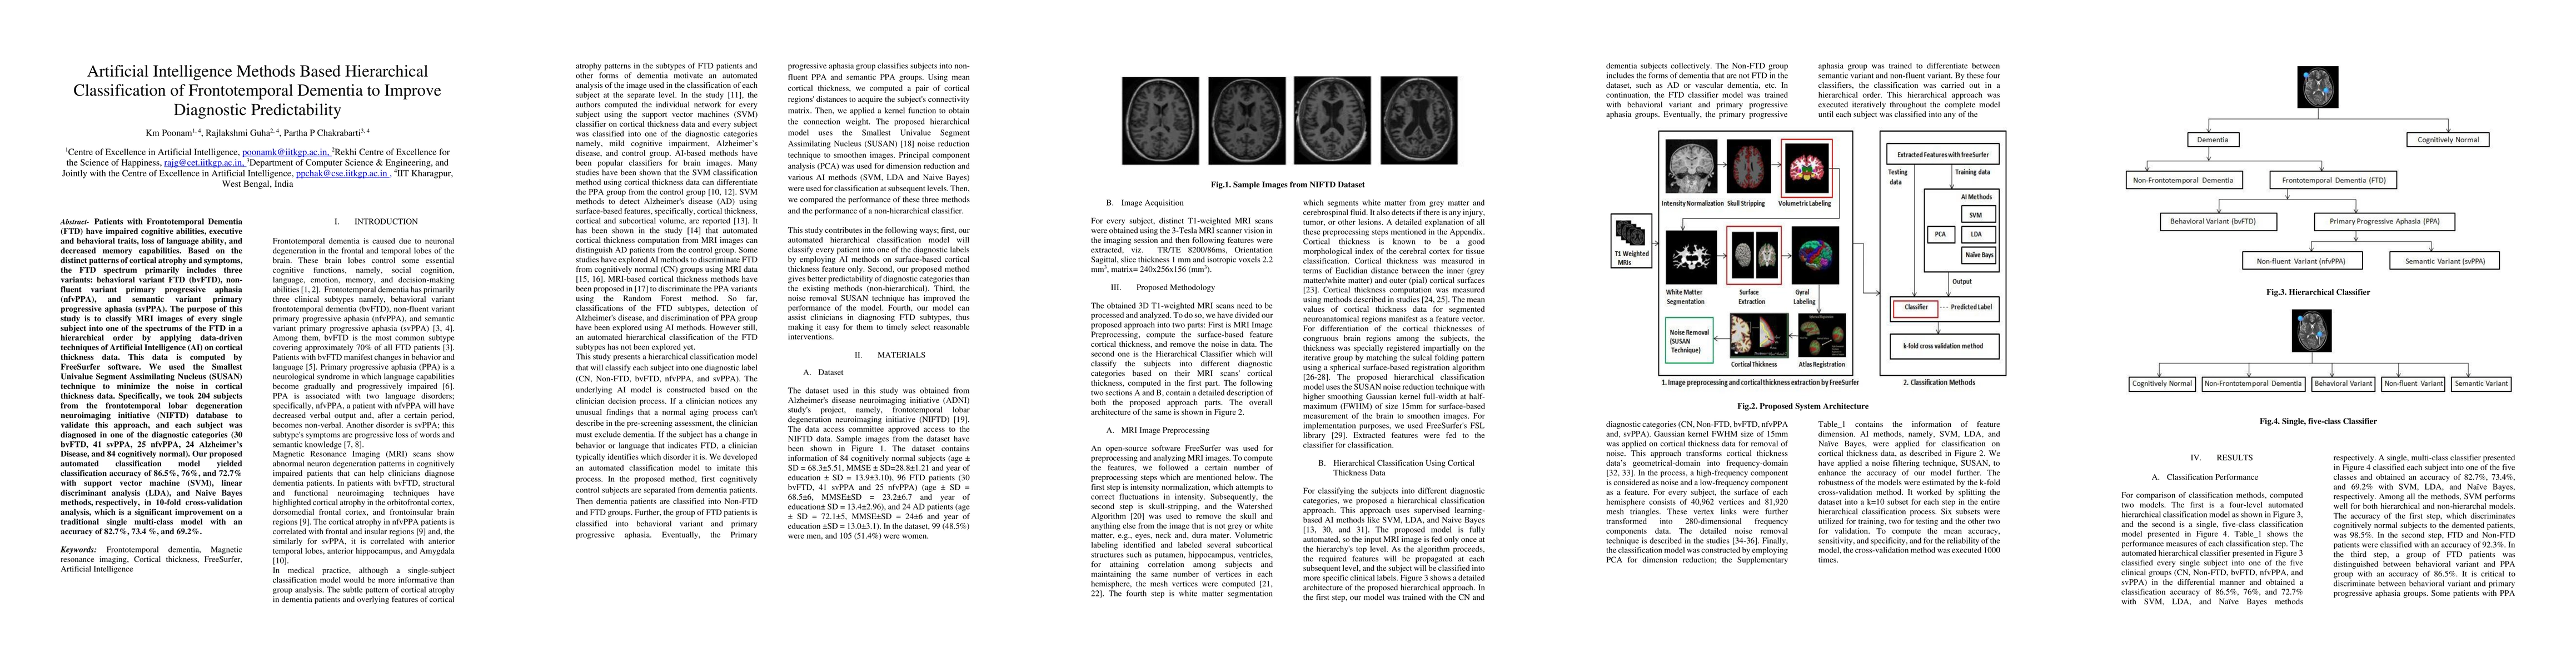

Patients with Frontotemporal Dementia (FTD) have impaired cognitive abilities, executive and behavioral traits, loss of language ability, and decreased memory capabilities. Based on the distinct patterns of cortical atrophy and symptoms, the FTD spectrum primarily includes three variants: behavioral variant FTD (bvFTD), non-fluent variant primary progressive aphasia (nfvPPA), and semantic variant primary progressive aphasia (svPPA). The purpose of this study is to classify MRI images of every single subject into one of the spectrums of the FTD in a hierarchical order by applying data-driven techniques of Artificial Intelligence (AI) on cortical thickness data. This data is computed by FreeSurfer software. We used the Smallest Univalue Segment Assimilating Nucleus (SUSAN) technique to minimize the noise in cortical thickness data. Specifically, we took 204 subjects from the frontotemporal lobar degeneration neuroimaging initiative (NIFTD) database to validate this approach, and each subject was diagnosed in one of the diagnostic categories (bvFTD, svPPA, nfvPPA and cognitively normal). Our proposed automated classification model yielded classification accuracy of 86.5, 76, and 72.7 with support vector machine (SVM), linear discriminant analysis (LDA), and Naive Bayes methods, respectively, in 10-fold cross-validation analysis, which is a significant improvement on a traditional single multi-class model with an accuracy of 82.7, 73.4, and 69.2.